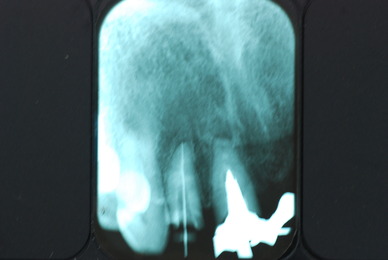

必ずばい菌が侵入しないようにしてばい菌である虫歯を除去します。

銀歯の下はばい菌だらけです。こういうのはよくあります。取り残しですね。![treatment_05[1]](https://livedoor.blogimg.jp/netdental/imgs/3/a/3ad019d0-s.jpg)